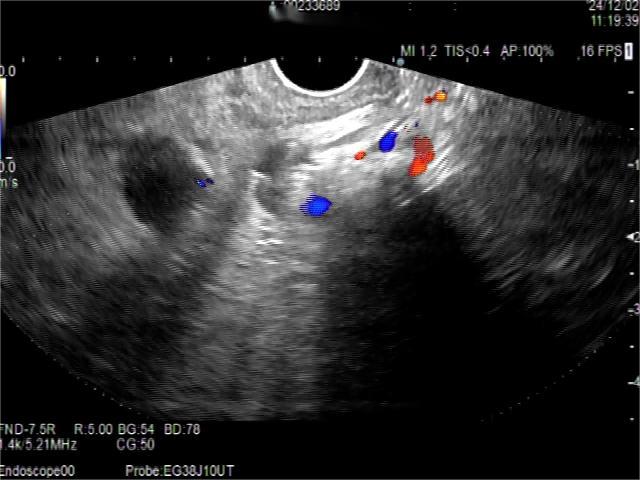

• 超声内镜引导下胃旁曲张静脉精准断流术治疗食管胃静脉曲张出血的疗效分析(附20例报告)

2025, 31(8):85-90. DOI: 10.12235/E20250036

摘要 (153) HTML (42) PDF 5.38 M (98) 评论 (0) 收藏

摘要:目的 探讨超声内镜引导下胃旁曲张静脉精准断流术治疗食管胃静脉曲张出血的疗效。方法 回顾性分析2024年1月1日-2024年12月31日于该院接受超声内镜引导下胃旁曲张静脉精准断流术治疗的20例肝硬化食管胃静脉曲张出血患者的临床资料,并评估治疗效果。结果 20例患者均顺利完成超声内镜引导下胃旁曲张静脉精准断流术;注射组织胶联合置入弹簧圈(16例)和单独注射组织胶(4例)均成功阻断胃旁来源的曲张静脉;所有患者均未发生穿孔、食管贲门狭窄、大出血、败血症和异位栓塞。1例单独注射组织胶的患者,术后胃旁曲张静脉少许渗血,经降低门静脉压力治疗3 d后好转,另1例单独注射组织胶患者,术后出现低热,抗感染3 d后体温恢复正常。结论 超声内镜引导下胃旁曲张静脉精准断流术治疗食管胃静脉曲张出血的临床疗效好,异位栓塞、大出血、感染和穿孔等并发症少,但仍需要密切随访,观察胃旁曲张静脉的排胶问题。